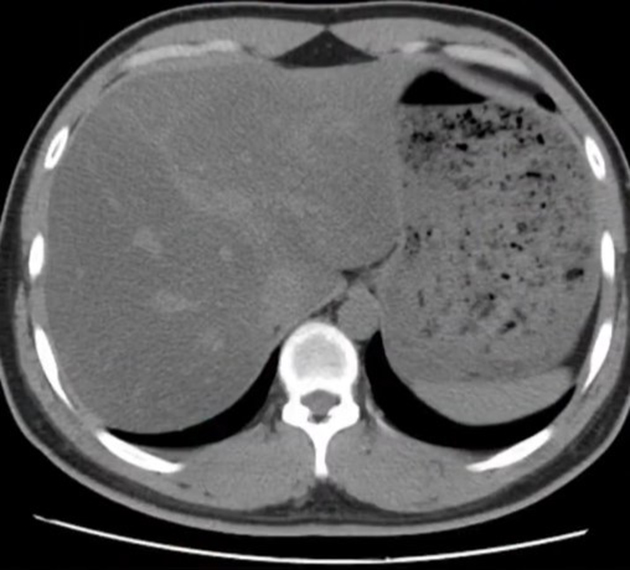

Sau vài tháng, cô giảm được 10kg, vòng eo nhỏ lại rõ rệt. Tuy nhiên, kết quả tái khám sau 6 tháng ăn như vậy lại khiến cô ngỡ ngàng. Dù chỉ nặng 47kg nhưng tình trạng gan nhiễm mỡ nhẹ không những không giảm đi mà tăng lên 2 cấp độ, đạt tới mức nặng kèm suy giảm chức năng thải độc gan và có sỏi thận nhỏ. Cô cũng bị suy giảm miễn dịch, rối loạn nội tiết (rụng tóc, chậm kinh) do ché độ ăn này.